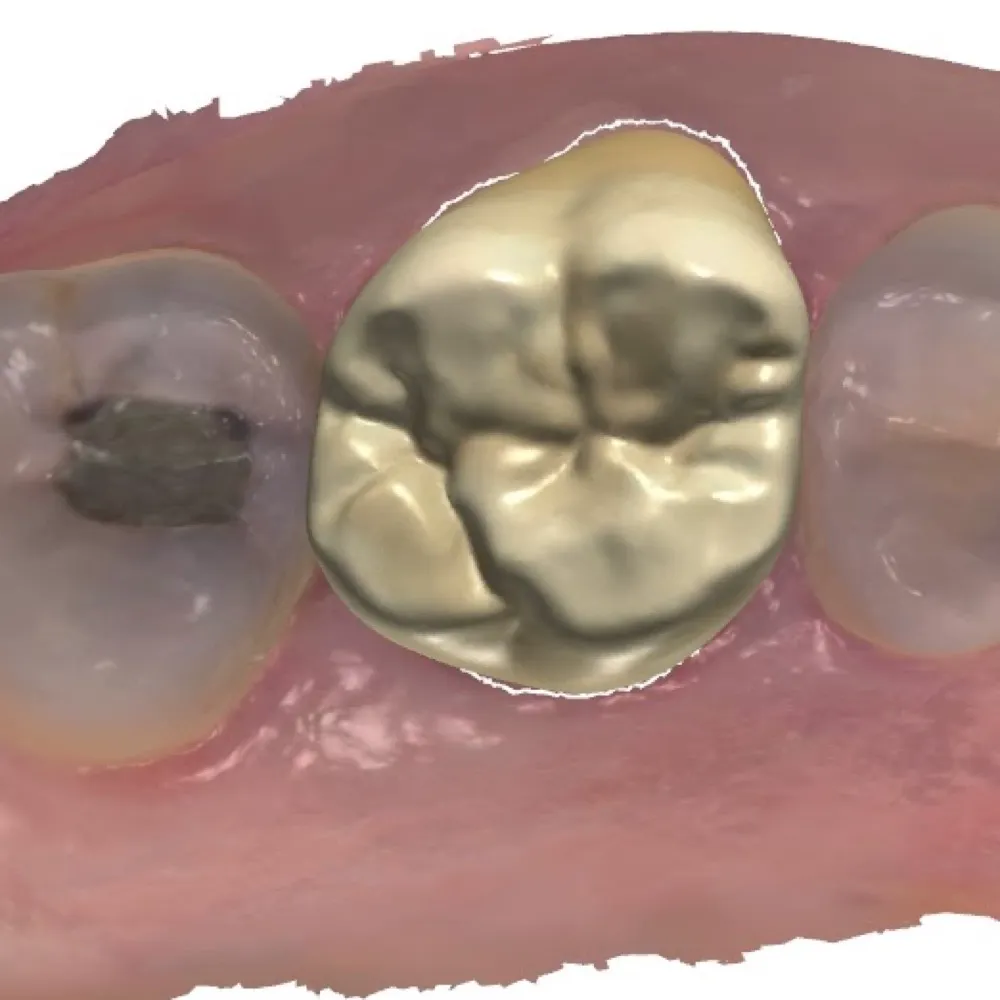

- Crown/Bridge